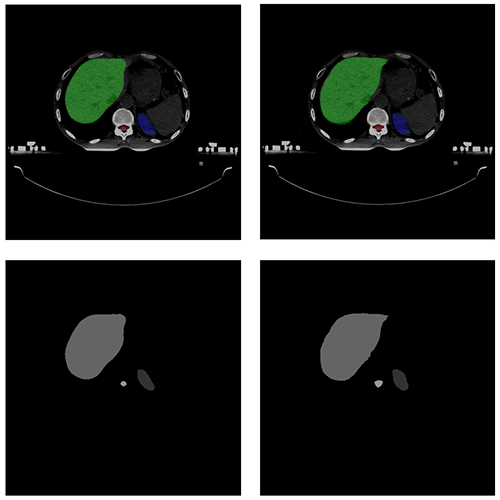

自動勾畫效果

AUTOMATIC CONTOURING

原圖

預測圖